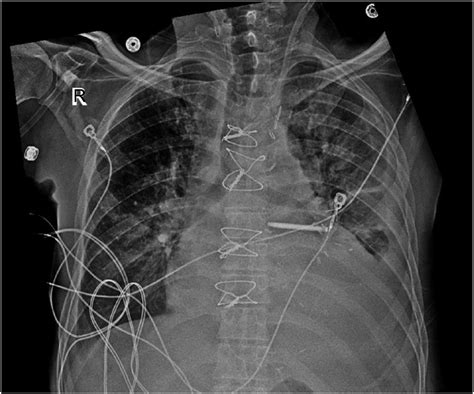

The procedure for Internal Jugular Vein Catheterization can be performed using either the landmark technique or ultrasound guidance. Ultrasound guidance is preferred due to its higher success rate and lower complication rate.

14. Connect the catheter to the desired infusion system and flush with saline.